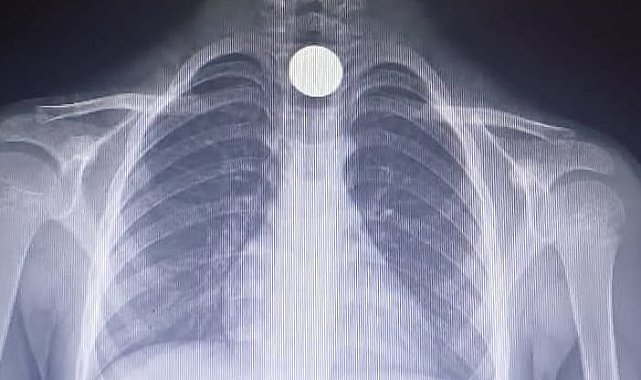

BURSA'nın İnegöl ilçesinde Yusuf Z.'nin (5) yemek borusuna takılan madeni para, operasyonla çıkartıldı. Olay, saat 14.00 sıralarında İnegöl ilçesi Mesudiye Mahallesi'nde meydana geldi. Sarmaşık Sokak'taki evlerinde oynayan Yusuf Z., fenalaşınca ailesi tarafından özel otomobille İnegöl Devlet Hastanesi'ne götürüldü. Tetkiklerde, yemek borusuna 50 kuruşluk madeni para kaçtığı tespit edilen Yusuf Z., ambulansla Bursa Yüksek İhtisas Eğitim ve Araştırma Hastanesi'ne sevk edildi. Yusuf Z.'nin yemek borusundaki para, burada yapılan başarılı ameliyatla çıkartıldı.

Yusuf'un yemek borusuna takılan madeni para operasyonla çıkartıldı

Yavuz YILMAZ/İNEGÖL (Bursa), (DHA)-BURSA'nın İnegöl ilçesinde Yusuf Z